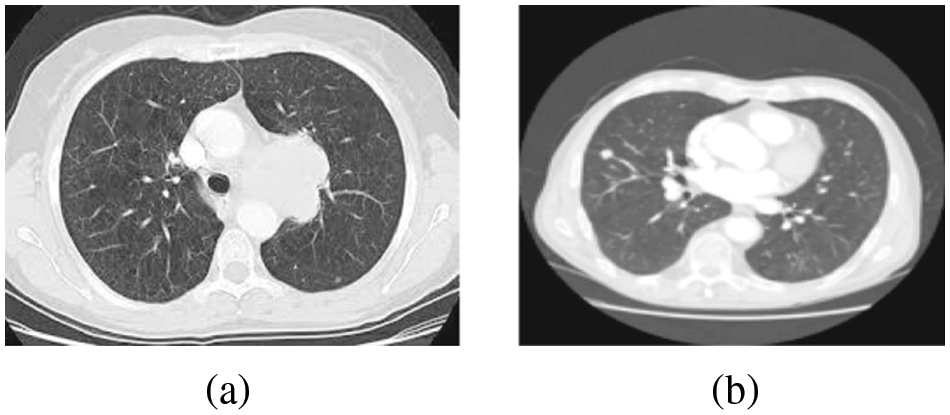

Figure 1: (a) Lung image (b) Diseased LC image